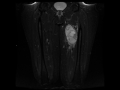

Myxofibrosarcoma grade 3

45-year-old male with a slowly enlarging left thigh mass. There is a well-circumscribed solid appearing T1 mildly heterogeneous but predominantly isointense, T2/STIR heterogeneously hyperintense, centrally necrotic peripherally enhancing mass in the mid medial left thigh. A small plane of fat is maintained between the lateralmost lesion boundary and the cortical margin of the left femoral diaphysis at that site. There is mild perilesional edema. A myxoid tumor of the soft tissues was favored. This lesion was found to be a grade 3 myxofibrosarcoma. Imaging features of myxoid soft tissue tumors include high signal intensity characteristics on T2 weighted images because of high water content. Lesions range from benign to malignant entities. Some of the benign etiologies include intramuscular myxoma, synovial cyst, bursa, ganglion and benign peripheral nerve sheath tumor. Malignant etiologies include myxoid leiomyosarcoma, myxoid liposarcoma, myxoid chondrosarcoma and myxoid fibrosarcoma. Treatment for the malignant subtypes is usually with preoperative chemoradiation therapy followed by gross total resection.